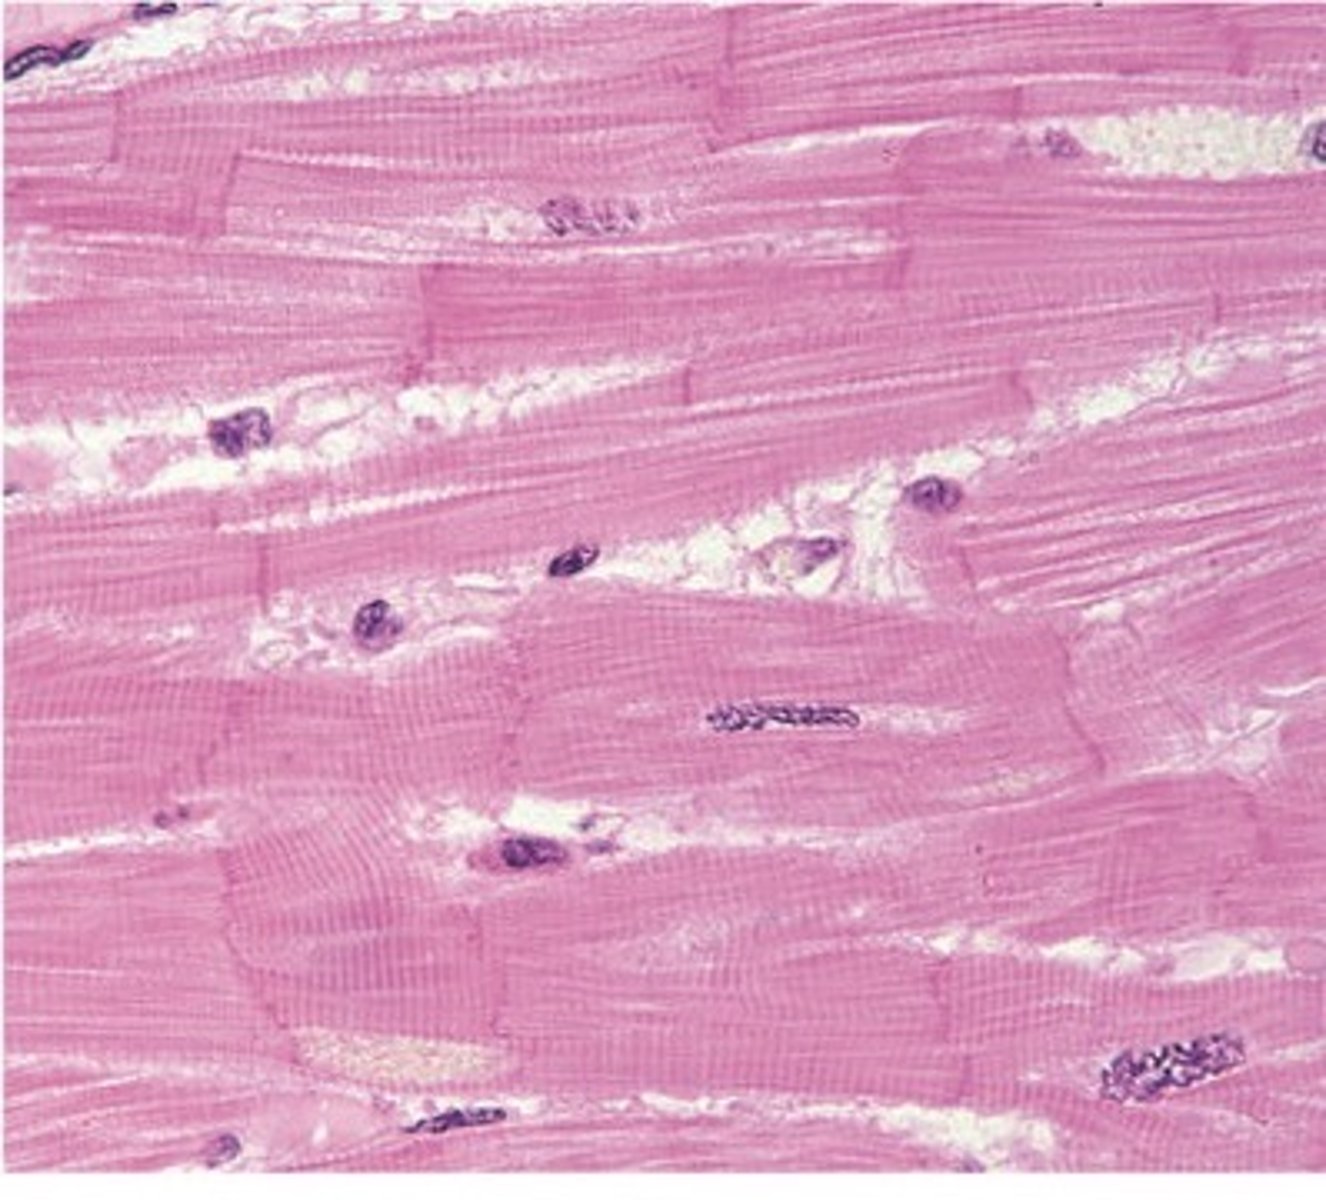

Which type of muscle tissue possesses striations?

skeletal and cardiac

what type of muscle in the image

skeletal

What type of muscle tissue is this?

cardiac